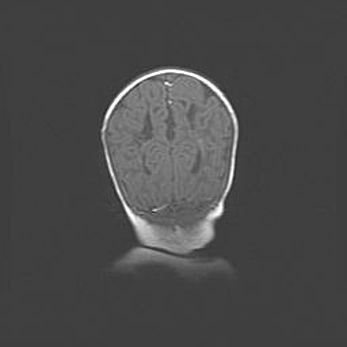

Наружная гидроцефалия с возможной атрофией височных областей.

Возраст: 28 дней

Вес: 3670 г

Пол: мужской

Окружность головы: 38 см

Срок гестации: 40 недель

Гидроцефалия головного мозга у новорожденных – это заболевание, которое характеризуется скоплением избыточного количества спинномозговой жидкости в желудочковой системе головного мозга в результате затруднения её перемещения от места выработки к месту поглощения в кровеносную систему или вследствие нарушения абсорбции. При открытой наружной форме гидроцефалии у новорожденных расширяются и переполняются субарахноидные пространства.

При нормотензивных  формах,  которые,  как  правило,  являются  следствием  перенесенных ишемических  повреждений  паренхимы  мозга,  возможно  сочетание микроцефалии  с нормотензивной гидроцефалией. В основе данных изменений лежит атрофия больших полушарий с преимущественной  локализацией  в  лобно-височных  областях.